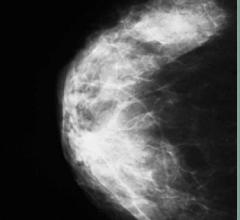

Mammography

Mammography is a breast imaging technique that uses X-rays to diagnose and locate tumors of the breasts.